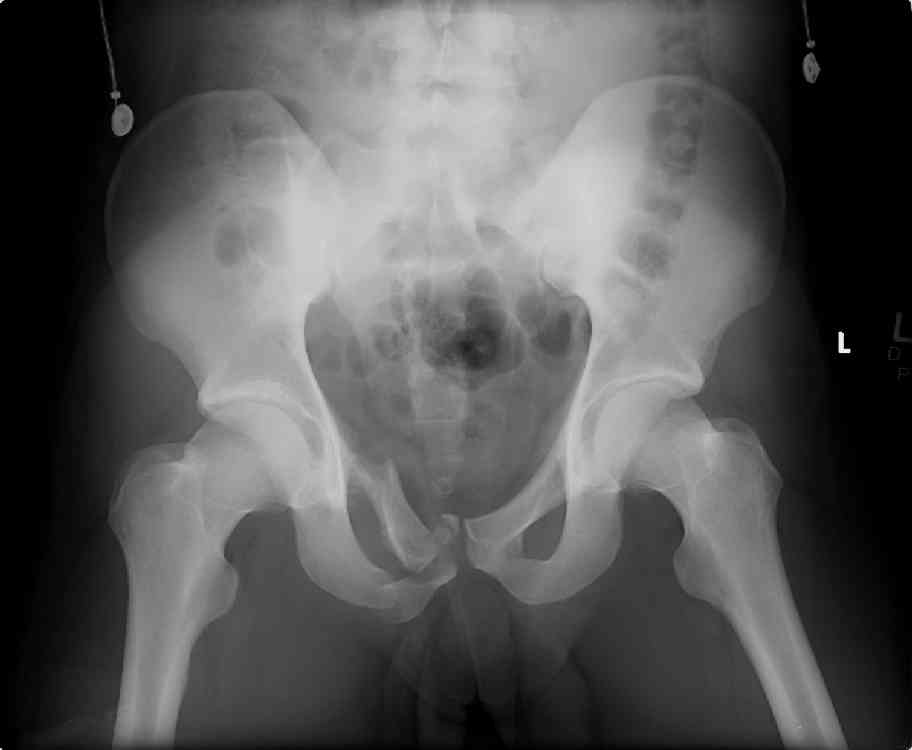

this is a healthy 22yo male. peds vs auto.

no other injuries. has anyone treated these non-operatively? thanks.